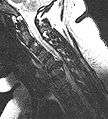

MRI scan of cervical disc herniation between fifth and sixth cervical vertebral bodies. Note that herniation between sixth and seventh cervical vertebral bodies is most common.

MRI scan of cervical disc herniation between sixth and seventh cervical vertebral bodies.